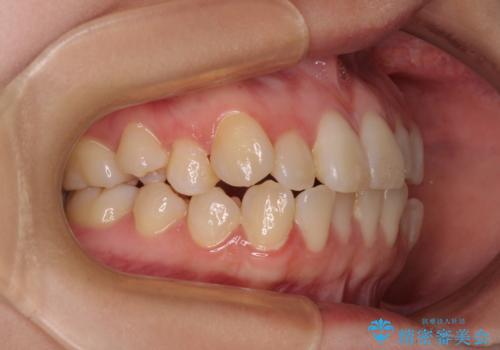

- 20代女性

- 患者様は「歯並び全体のデコボコが気になり、人前で笑うことに抵抗がある」とのことでご来院されました。

診査の結果、上下顎ともに叢生が認められましたが、ワイヤー矯正・マウスピース矯正のいずれでも対応可能な症例でした。